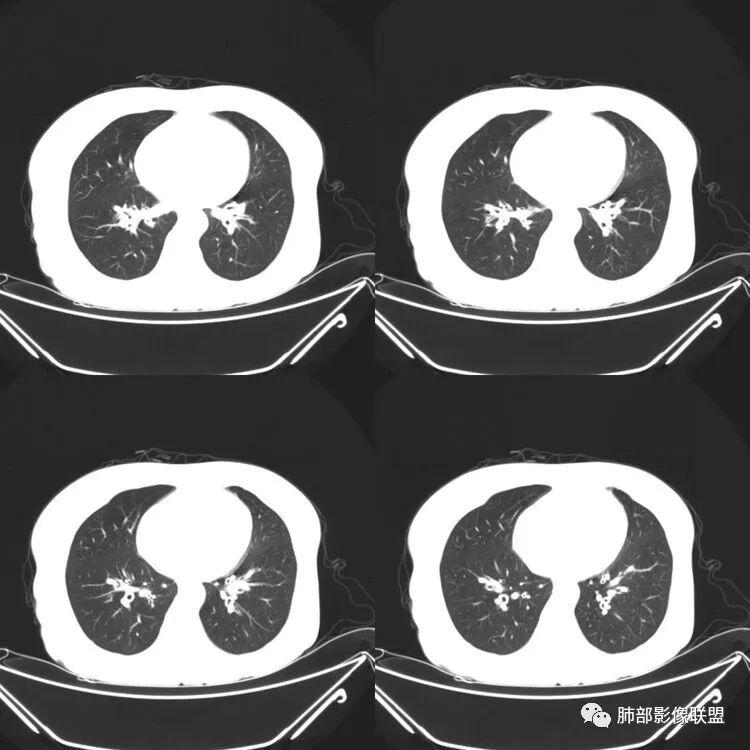

患者,女,64岁,反复咳嗽、咳痰、胸闷10年,加重2周患者10余年来每当受凉感冒出现咳嗽、咳痰、胸闷,有时痰中带血,输液治疗(具体不详)可好转。既往有声带肥厚手术病史。CT示气管、主支气管及分支支气管管壁弥漫性增厚累及膜部,局部伴钙化,管腔狭窄,考虑淀粉样变性

患者,女,64岁,反复咳嗽、咳痰、胸闷10年,加重2周。气管支气管及两肺下叶 支气管弥漫性的环状增厚,管腔扩张,管腔感觉比较松弛。第一感觉,气管支气管淀粉样变。鉴别诊断,1、支气管内膜结核,肺内散在一些支气管的播散病灶,粟粒结节为主,形态比较单一。2、复发性的多软骨炎,就得了解一下其他部位,有没有多个部位的软骨炎。这个病人右侧胸廓缩小,升主动脉明显的扩张,其横径明显的超过了降主动脉。

征象很明确

弥漫支气管壁增厚,膜部受累

声带肥厚——受累

隐约见钙化

南边:肺部有肺气肿支气管腔狭窄淀粉样变性?复发性多软骨炎?血管炎?慢支?结核?曲霉菌?南边:一般还是淀粉样变性与复发性多软骨炎鉴别其次就是支气管骨化症,但是骨化下朝上,且壁结节状钙化明显,本例不太支持。至于结核、曲霉菌?1.结核,一般不会这么广泛,支气管壁狭窄后扩张2.曲霉菌可以这么广泛,但是支气管壁管腔扩张,而且附近脂肪间隙有炎性反应,不太支持;3.血管炎,一般合并肺内有病灶,但是声带受累,放待排;4.软骨炎一般全身受累,例如耳廓等;而且膜部不受累,不太支持;倾向于淀粉样变性;淀粉分很多型,气管支气管是最常见的。尘缘:影像上生理性钙化与支气管骨化无法区别,镜检也不好鉴别,需要依赖活检,看粘膜中是否合并炎性改变(淋巴细胞,组织细胞等炎性细胞侵润)来鉴别Coke with ice:经常看到的这种是老年性肺改变,又称年龄相关肺改变。气管和支气管弥漫性软骨钙化,常见老年女性。尘缘:支气管骨化症很罕见的,所以绝大多数还是生理性钙化。对于老年人,无临床症状的钙化,还是基本上都是生理性钙化,无临床意义。大雄:如果管壁钙化伴明显增厚 影像还是提示一下建议支气管镜稳妥些

病理结果:肺淀粉样变

气管支气管淀粉样变性

三、影像表现

1.气管支气管型

①气管支气管壁增厚,形成粘膜下斑块与结节

②管腔广泛狭窄、闭塞

③管壁钙化

④膜部受累(具有重要鉴别意义)